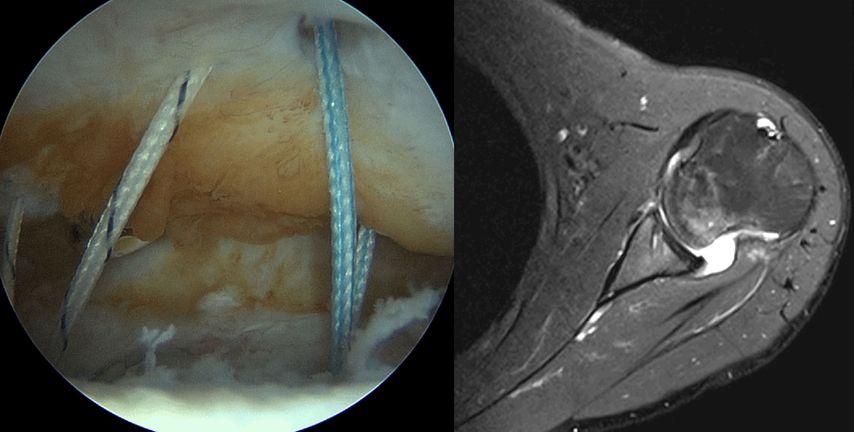

Zusätzlich zur Kapsel-Labrum-Refixation wird in zunehmendem Maße eine Remplissage (unanatomische Kapsulotenodese der Infraspinatussehne) empfohlen, dies insbesondere bei Revisionseingriffen, bei sehr sportlichen Patienten, besonders Kontaktsportlern und Patienten mit hohem funktionellem Anspruch und einer hohen Rezidivgefahr57,58 (Abb. 4a, 4b). Ursprünglich für Patienten mit großen Hill-Sachs-Defekten empfohlen („off-track“ Läsionen), ist in jüngerer Zeit eine deutlich großzügigere Indikationsstellung zur Remplissage auch bei „on-track“ Läsionen festzustellen.59 Für arthroskopische Bankartoperationen mit zusätzlicher Remplissage sind deutlich geringere Versagerraten und bessere Sportfähigkeit beschrieben.60 Die früher beklagte signifikante Einschränkung der Beweglichkeit nach einer Remplissage konnte in der neueren Literatur nicht bestätigt werden.61

Abb. 4a, b: Zusätzlich zur Kapsel-Labrum-Refixation wird in zunehmendem Maße eine Remplissage empfohlen, dies insbesondere bei Revisionseingriffen, bei sehr sportlichen Patienten mit hohem funktionellem Anspruch und einer hohen Rezidivgefahr